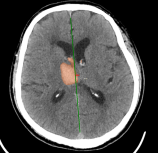

Chẩn đoán hình ảnh mô mềm tiên tiến cho vùng bụng.

Tăng cường độ tương phản I-ốt.

Hỗ trợ đánh giá an toàn cho bệnh nhân.

Đảm bảo hình ảnh chất lượng cao.